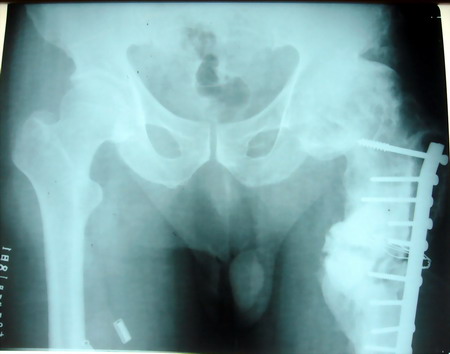

以下是引用天南地北在2007-7-19 12:37:00的发言:[br]左股骨头符合缺血性坏死[br]左股骨中上段骨折愈合不良

以下是引用jiangjing在2007-7-20 16:17:00的发言:[br]左股骨头符合缺血性坏死[br]左股骨中上段骨折愈合不良